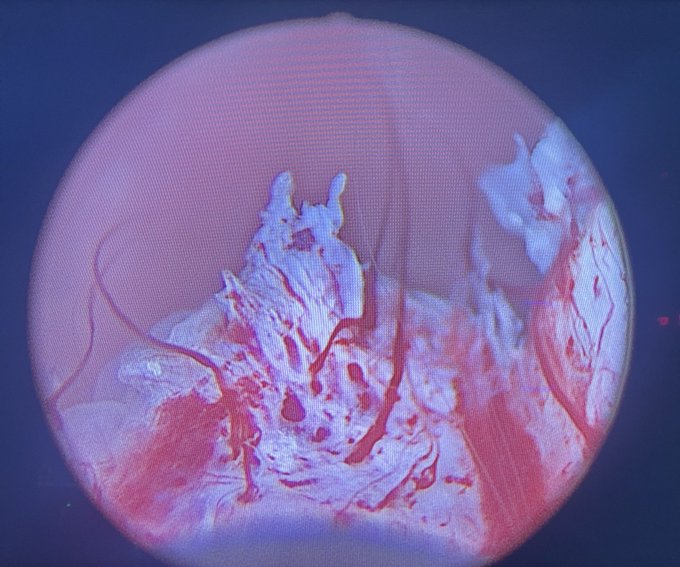

From the desk of Perry Xu, MD (@perryjxu): -Dr. Xu is seeing more patients post-aquablation with persistent gross hematuria and LUTS. -Here are some endoscopic images post-aquablation (6 months to a year ago). Most impressively, one patient had fused vessels across the aqua…

-Dr. Xu is seeing more patients post-aquablation with persistent gross hematuria and LUTS.

-Here are some endoscopic images post-aquablation (6 months to a year ago). Most impressively, one patient had fused vessels across the aqua…